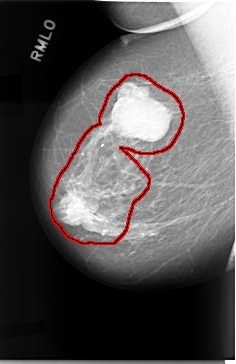

FILE: C_0019_1.RIGHT_MLO.OVERLAY

TOTAL_ABNORMALITIES 1

ABNORMALITY 1

LESION_TYPE MASS SHAPE LOBULATED MARGINS CIRCUMSCRIBED

ASSESSMENT 5

SUBTLETY 5

PATHOLOGY MALIGNANT

TOTAL_OUTLINES 1

BOUNDARY